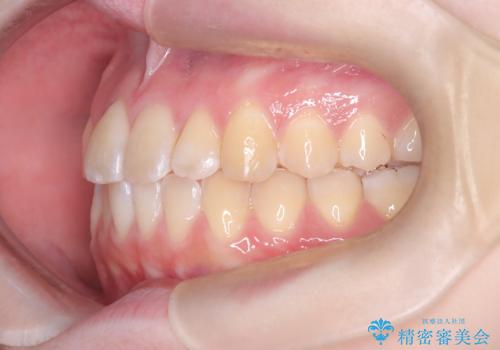

【インビザライン】オープンバイト。凸凹を治したい

- オープンバイトを主訴に来院されました。

インビザラインを用いIPRと遠心移動を行いオープンバイトと叢生の改善を行なっております。

前歯の叢生がわずかにありますが、追加アライナーの作成は希望されなかったため、歯を動かしていく動的治療は終了となりました。